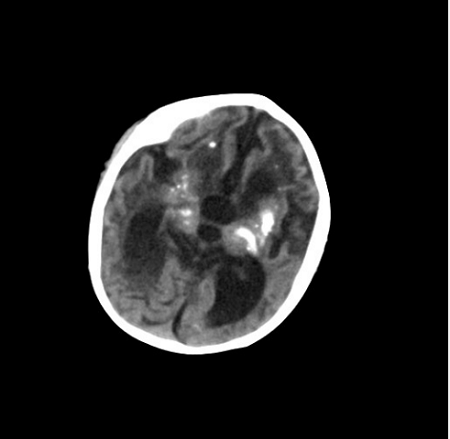

AGS临床表现非常的多样,个体间的差异也较大。多数患儿在3岁前就发病了,最常见的症状为颅内钙化、脑白质病变、脑萎缩,可伴有肌张力增高(就是肌肉紧张度增高)、运动发育落后、语言发育落后、小头畸形,伴或不伴智力发育落后等。其中颅内钙化在头颅CT上显示较清楚,多为双侧,主要分布于基底节区(图1)。脑白质病变在头颅MRI上显示较清楚,可累及脑室周围、皮质下白质、额叶和颞区等部位(图2)。脑萎缩主要显示为脑室周围区域和脑沟的扩大(图3)。也有患儿以反复发生冻疮样皮疹为突出表现,多发生在四肢末端、耳朵、面部和肘部等部位(图4),这些孩子的皮疹在冬天加重,气温变暖后可好转。如孩子出现上述症状,需及时到医院就诊。其他的临床表现还包括发热、癫痫、白细胞减少、贫血、血小板减低、转氨酶升高、肝脾肿大、肺部间质病变、甲状腺功能减退或者亚临床甲状腺功能减退、胃食管反流、关节肿胀或疼痛。轻度肺间质病变可以仅表现为肺部影像学的异常,严重者可以出现咳嗽、呼吸困难等症状。如果孩子出现了上述表现,家长切莫大意,要及时带孩子到正规医院就诊哦!

图1